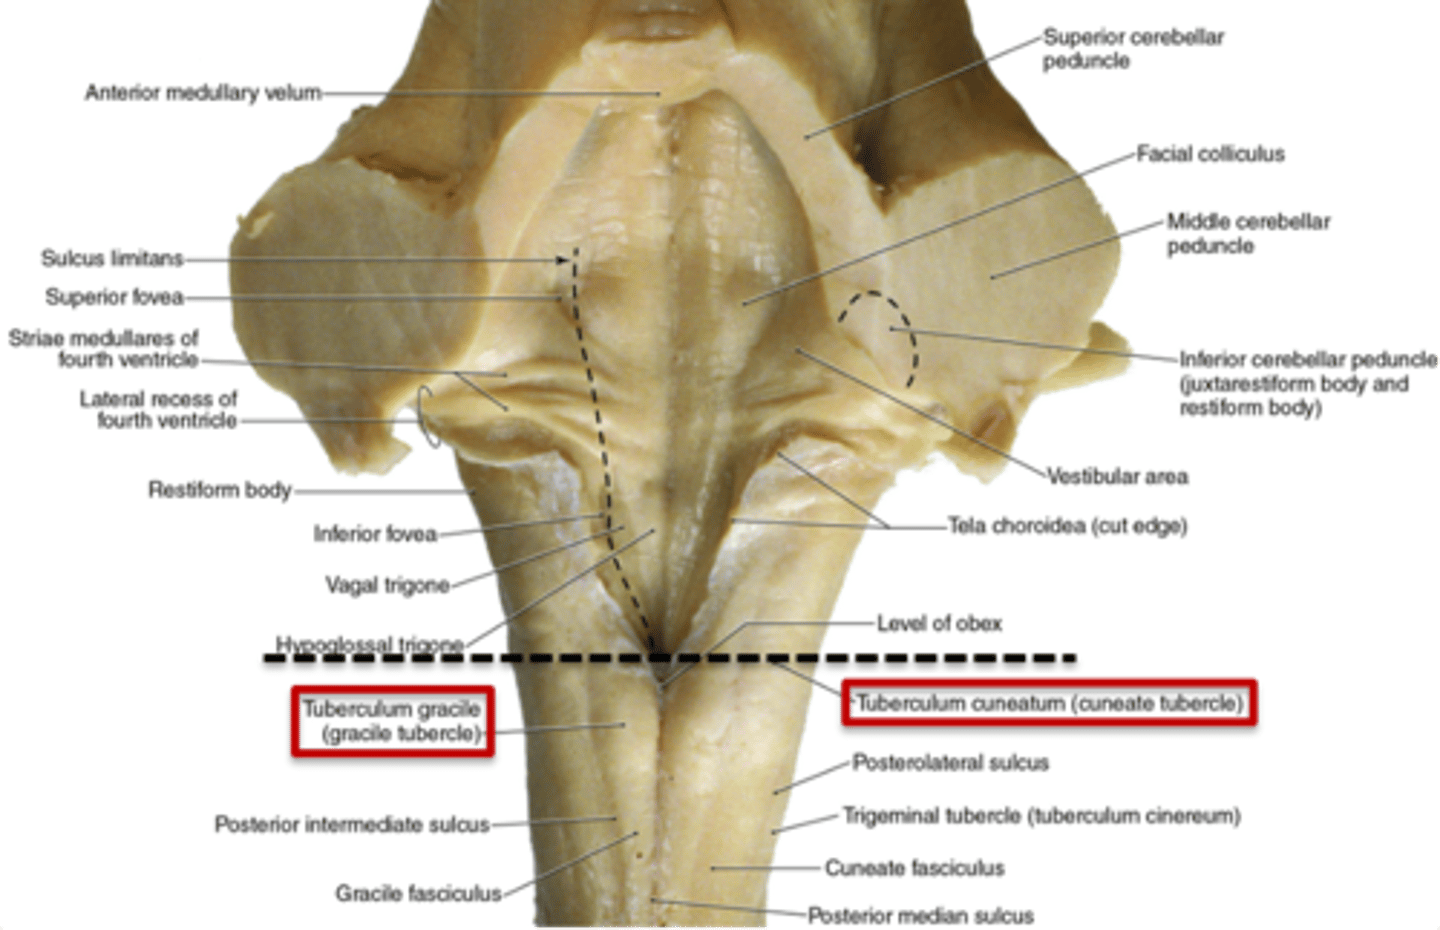

what are the 2 tubercles found on the closed (caudal) medulla?

1. gracile tubercles (more medial, touch/proprioception from lower body)

2. cuneate tubercles (more lateral, touch/proprioception from upper body)